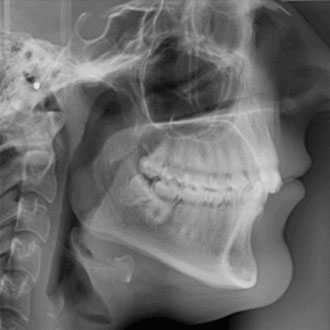

Cephalometric radiography provides a complete view of the dento-maxillo facial region. The functionally designed and easy to use head positioner ensures accurate patient positioning in lateral a.p and p.a technique.

Diagnostic Tests / Digital OPG. ... An Orthopantomogram (OPG), also known as an "orthopantogram" or "panorex", is a panoramic scanning dental X-ray of the upper and lower jaw. It shows a three-dimensional view of a half-circle from ear to ear.